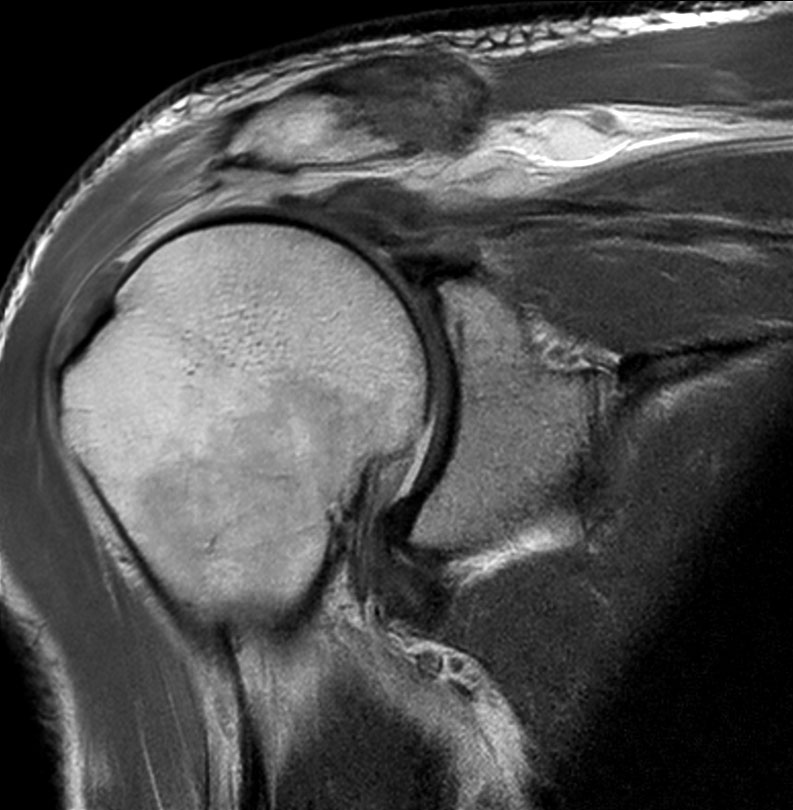

Shoulder imaging using ComforTone